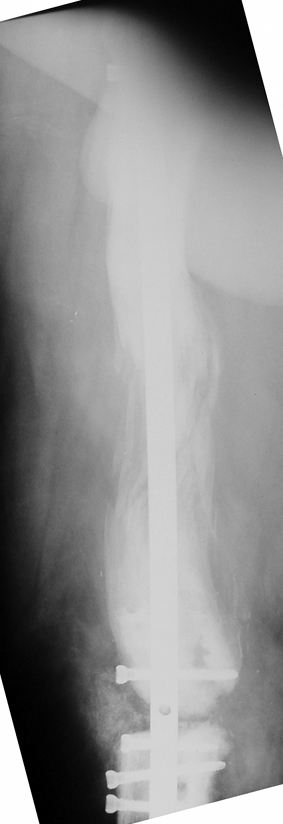

The duration of external fixation (external fixation index) depends on the amount of distraction required, and the extremity is prone to complications during this period. After the distraction phase is completed, the external fixator remains in place during the consolidation phase, which lasts twice as long as the distraction phase; but this period is hardly tolerated. If the external fixator is removed before sufficient consolidation is achieved, fractures, deformity and shortness will be the result. In our department, ‘lenghthening over nail’ method is used in order to decrease the external fixation index and increase patient comfort and activity level. In this method, the intramedullary nail is statically locked after the completion of the distraction phase, and external fixator is removed. The extremity is stabilized by the intramedullary nail during consolidation phase. In this way, complications due to long external fixation index or early removal of the external fixator are avoided.

Case 3